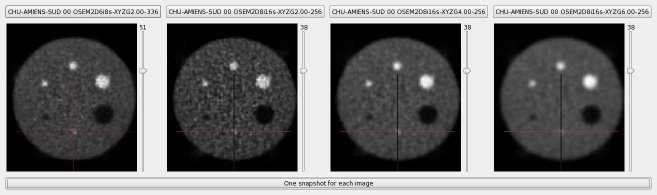

All reconstructions can also be compared visually :